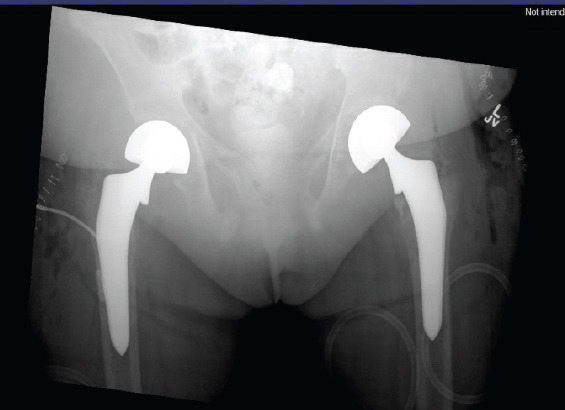

Case report: We present the case of a 50-year-old African American female with a history of ESRD on dialysis, who presented with bilateral hip pain after a minor fall. Imaging revealed bilateral displaced femoral neck fractures. Laboratory workup showed a hemoglobin level of 7.4 g/dL and microcytic anemia. Due to her chronic kidney disease, she was diagnosed with renal osteodystrophy, contributing to bone fragility. A rare Cromer blood group antibody was also detected, complicating transfusion planning. She underwent surgical repair of both hips, and her post-operative management involved coordinated multidisciplinary care addressing orthopedic, hematologic, and nephrologic concerns.